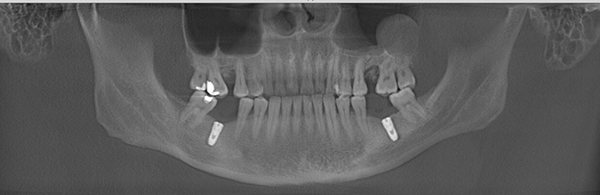

王先生术后牙齿全景片